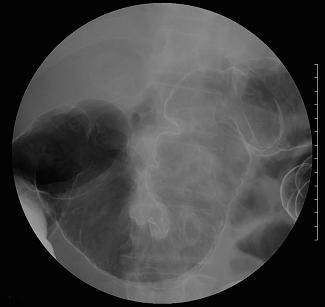

A case of idiopathic mesenteric phlebosclerosis (phlebosclerotic colitis).

Inflammatory or ulcerative disease / lesions/phlebosclerotic colitis

Large intestine(Colon)/More than one of the above

X-ray